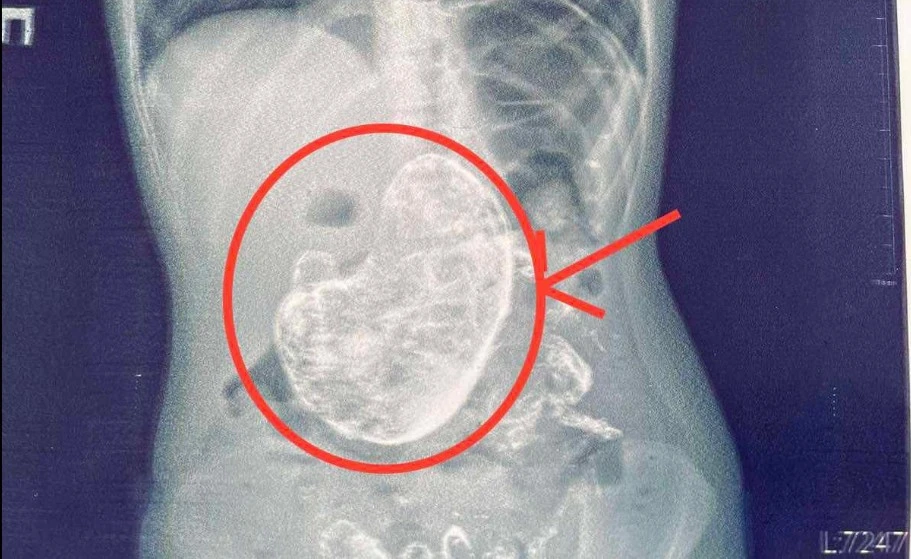

"Rtg исследование желудочно-кишечного тракта помогло обнаружить постороннее тело в желудке, а ФЭГДС подтвердила наличие трихобезоара", – объясняет Тарас Мельник.

Благодаря слаженной работе команды гастроэнтерологов, анестезиологов и хирургов ребенка успешно прооперировали, а инородное тело, сформированное из волос весом 1 кг, удалили.